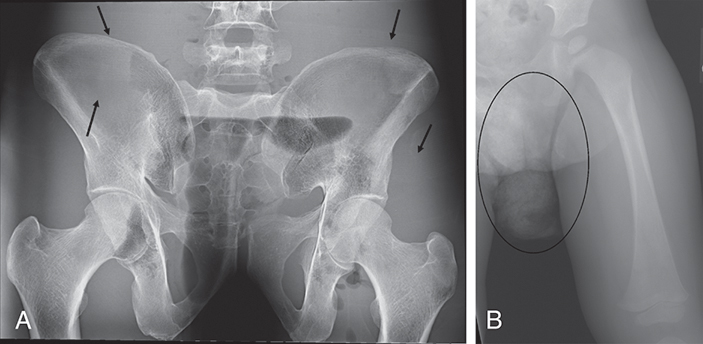

In Fig. 4.29A, the technologist failed to remove the patient’s elastic-waist shorts. The elastic appears as small radiopaque lines running through the wings of the pelvis. Owing to the sensitivity of most digital image receptors, clothing, especially bulky clothing, should be removed if it is in the anatomy of interest. Fig. 4.29B is a pediatric femur and the patient has a wet diaper. In this instance, the diaper is not obscuring any pertinent anatomy. Care must also be taken when imaging a patient in a t-shirt that has heavy graphics (Fig. 4.30A), beads (Fig. 4.30B), or metallic paint (Fig. 4.30C). These can show artifacts within the chest area and be mistaken for pathology.